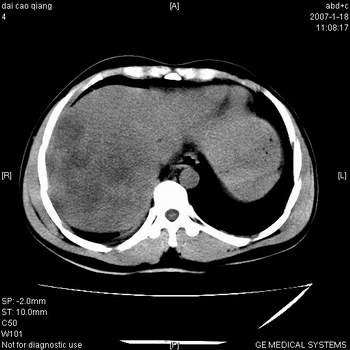

符合巨块型肝癌表现:

1、平扫低密度,增强后表现为快进快出。

2、动脉期可见迂曲的动脉供血血管

3、并可见门静脉右支癌栓形成

4、可见假包膜

5、腹主动脉旁结节影,考虑肿大淋巴结。

肝右叶巨大不均匀低密度肿块,前缘有假包膜,增强明显的呈快进快出表现,门脉右支有癌栓,病人虽然年轻但还是首先考虑肝右叶巨块形肝癌,病人血象高只能说有合并感染。不支持肝脓肿。